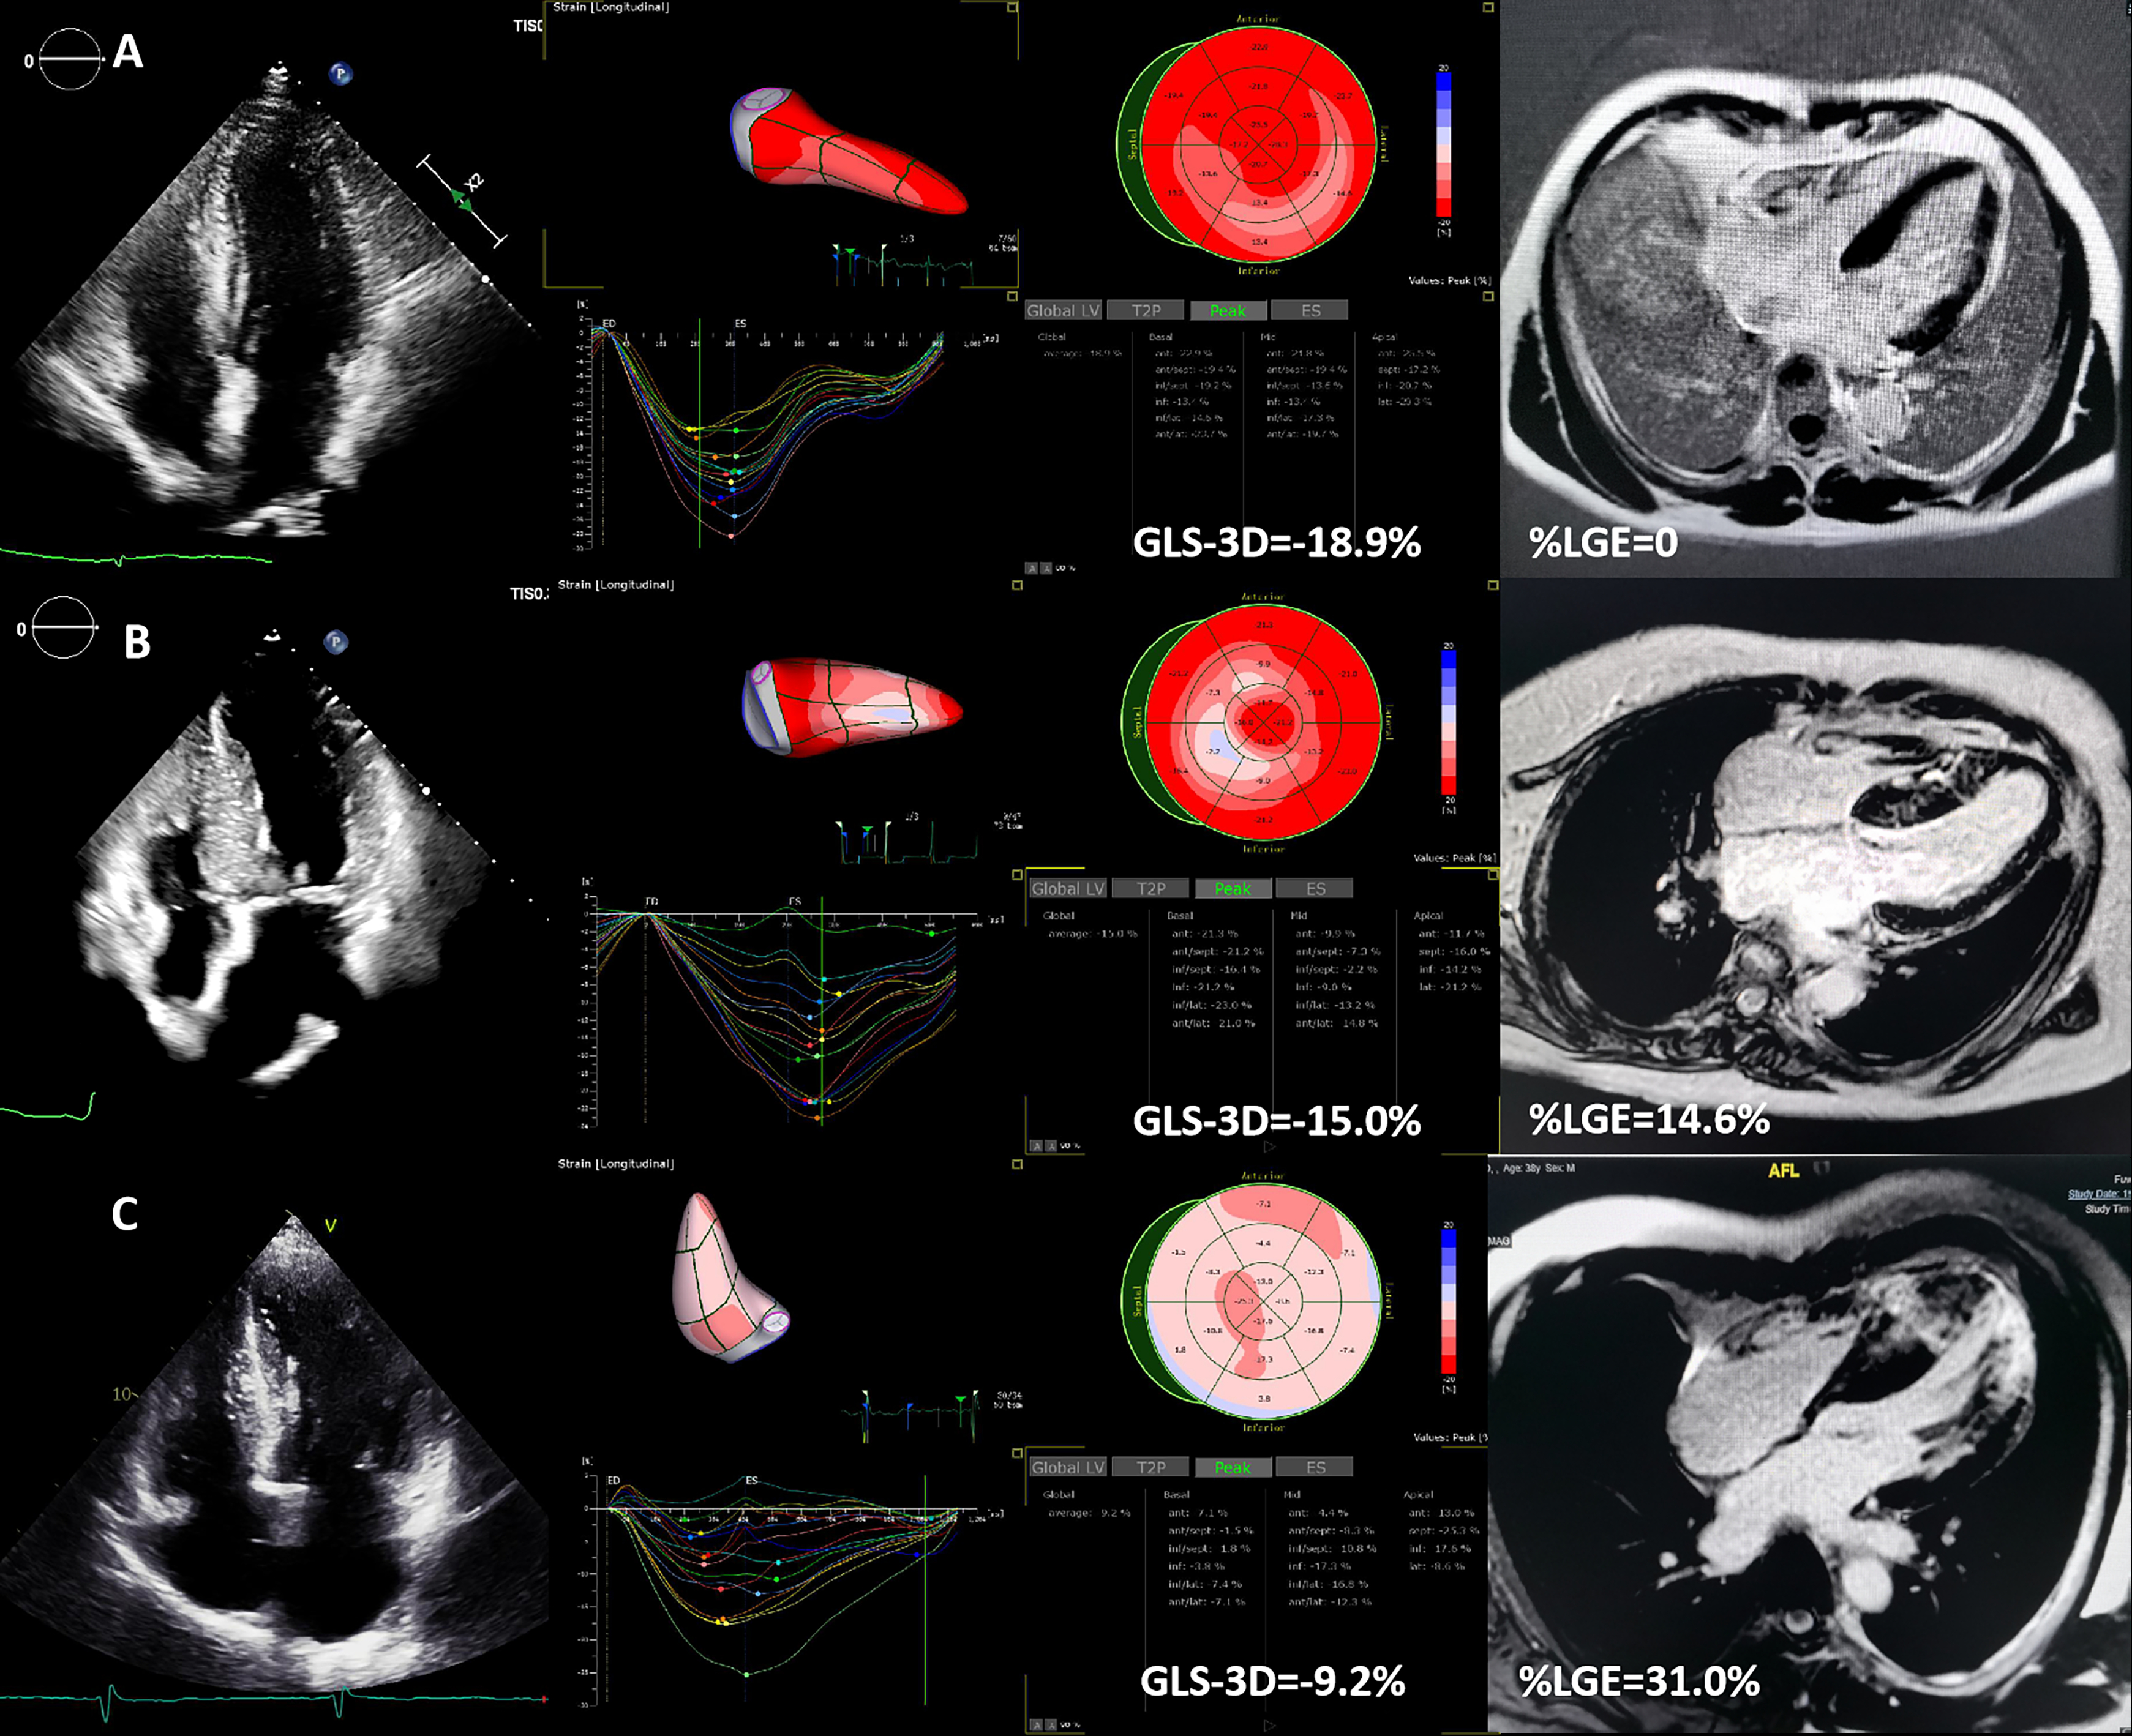

Using Three-Dimensional Strain Deformation Imaging To Quantify Replacement Fibrosis In Hypertrophic Cardiomyopathy

Abstract Body (Do not enter title and authors here): Background Three-dimensional speckle tracking deformation STE (3D-STE) can overcome some limitations of 2D imaging. This study aims to verify the feasibility of using 3D-STE to quantify replacement fibrosis against enhanced cardiac magnetic resonance imaging (CMR-LGE).

Method 3D-STE and the extent of LGE (%LGE) were prospectively measured in a large cohort of HCM patients, with an interval ≦ of 72 hours.

Results 511 HCM patients (age 49.0 ± 14.3 years; 66.5% male) were enrolled. Three-dimensional global longitudinal strain (GLS-3D) moderately correlated with GLS-2D (r=0.622, p=0.000). GLS-3D showed the strongest correlation with %LGE (r = 0.699, p < 0.001). A quadratic model (R2=0.448, p=0.000) for the relationship between GLS-3D and %LGE performed better than a linear model. GLS-3D (OR = 0.632, p < 0.001) was independently associated with extensive LGE (%LGE≧15%). GLS-3D exhibited the highest area under the curve (AUC 0.894, p < 0.001) for detecting extensive LGE With a cutoff of -15.25%, sensitivity 87.3%, specificity 78.3%.

Conclusion GLS-3D is the most strongly correlated with %LGE among all strain parameters, demonstrating potential as a surrogate marker for LGE in HCM.